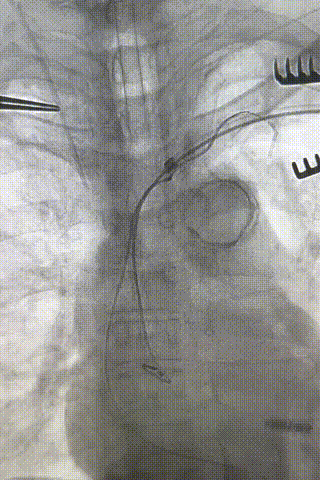

心室电极拔除:因锁定钢丝牵引力不足,以外鞘前向分离为主,激光鞘辅助消蚀,逐步分离粘连组织(图23-36),耗时近1小时,激光鞘联合外鞘经三尖瓣进入心室,发现电极与心室壁严重粘连。因牵引力不足,术者凭借心脏解剖经验精准调整角度,利用激光鞘逐步分离粘连组织,最终经外鞘成功剥离电极,可见长段粘连组织(图27-30)。

图27-30